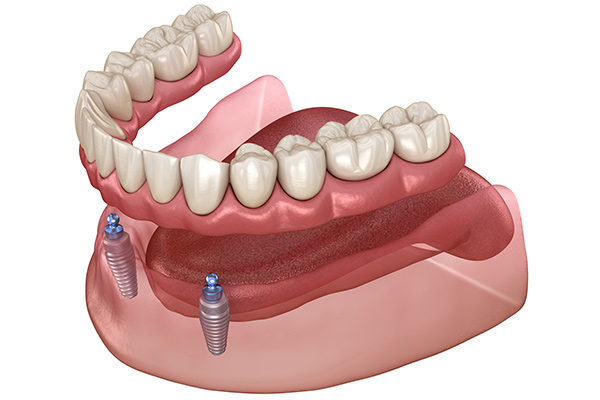

総入れ歯のお悩みを解消するインプラント

すべての歯を失って総入れ歯を使用しているものの、グラついて噛めない、違和感が大きいとお困りの患者さまにおすすめするのが「インプラントオーバーデンチャー」です。

これは、あごの骨に少数のインプラント(2~4本程度)を埋入し、それを固定源として入れ歯を安定させる治療法です。入れ歯が強力に固定されるため、外れる心配がなくなり、しっかり噛めるようになります。総インプラントよりも費用面での負担を抑えられることも大きなメリットです。